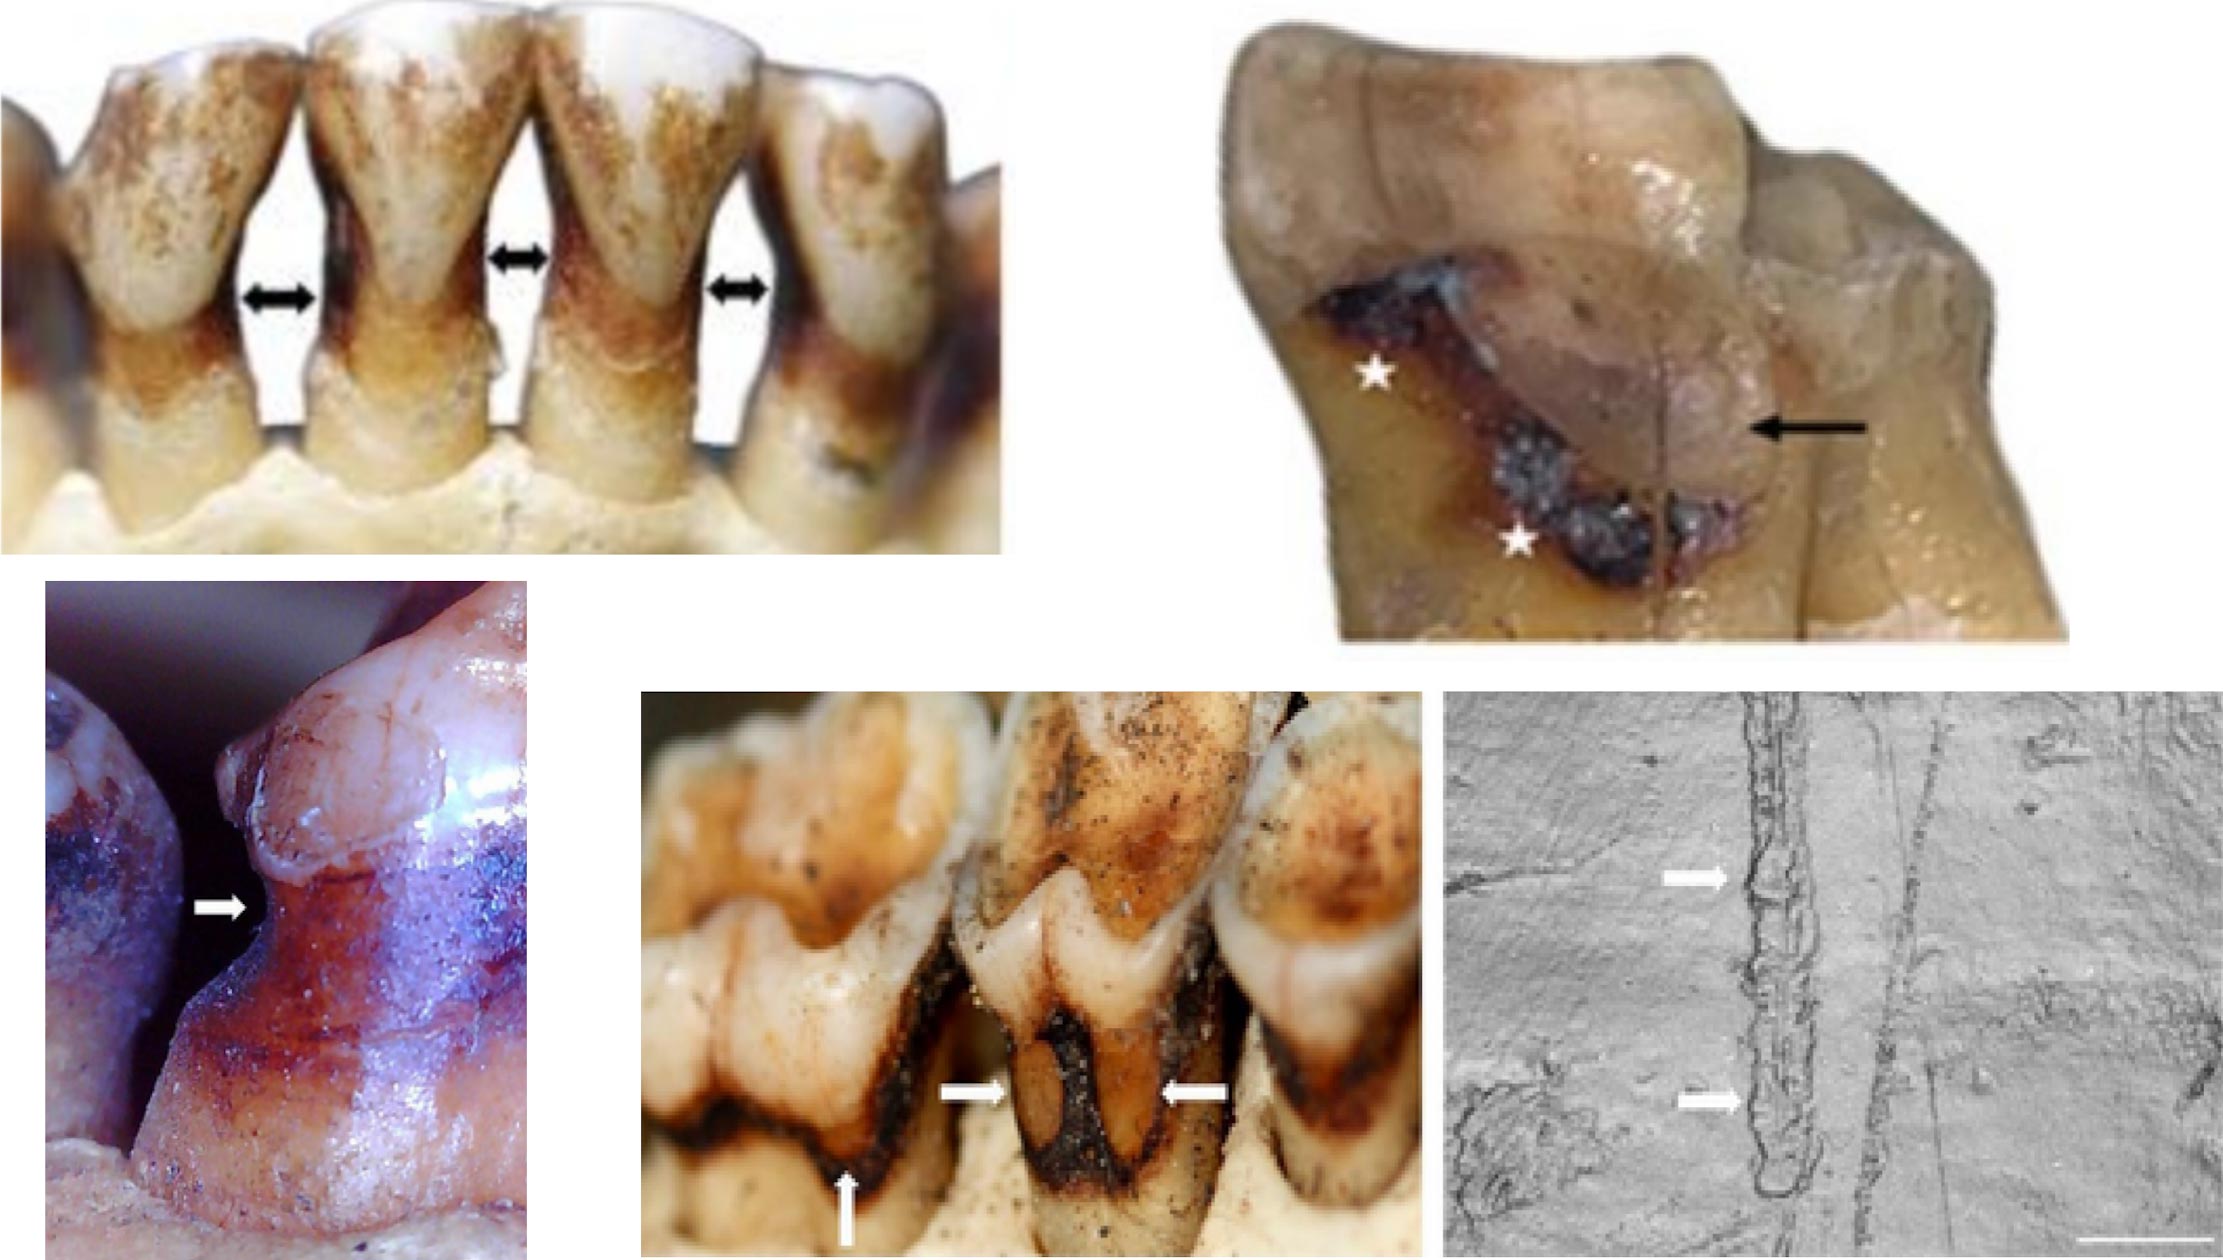

结果显示,大约4%的个体存在此类病变,部分沟槽在形态上几乎与化石人类的经典“牙签沟”无异:位置接近牙根、形状细长并逐渐变尖,沟内还能观察到平行细微划痕。另一些病变则表现为浅表、光滑的面状磨耗,尤其常见于前牙,研究者推测与许多灵长类大量摄入酸性水果有关。这表明,咀嚼过程中的自然磨耗、粗糙食物或夹杂的细砂,以及用牙齿剥离植物的习性,都可能在牙根部形成类似沟槽,未必涉及专门的“剔牙工具”。

更引人注目的是“缺席”的证据:在这批涵盖坚硬食性和强大咀嚼力物种的样本中,研究者没有发现任何一例楔状缺损。这类沿牙龈线向牙体内凿出的深V形缺口,在现代牙科诊疗中极为常见,通常被认为与磨牙、用力刷牙或频繁暴露于酸性饮品等因素相关,其在化石记录中的缺失一直让学界困惑。最新数据支持一个大胆推论——楔状缺损很可能是高度“现代化”的人类牙病,与自然咀嚼力的关系远小于与生活方式的关系。